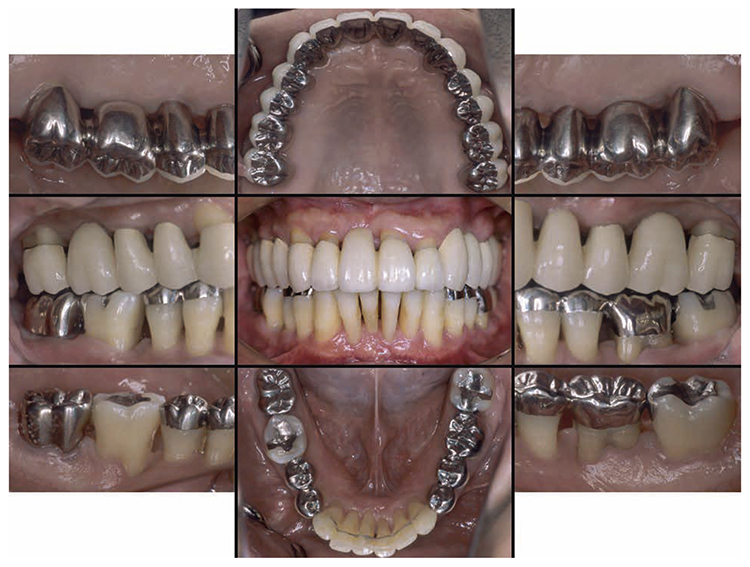

After orthodontic treatment was completed, fabrication of the final prosthesis was started.. Preliminary impression of the maxilla and mandible were taken, anatomic facebow and checkbite were obtained, and prosthetic diagnosis was performed. In the treatment plan before surgery, the first choice for the maxilla was the full mouth bridge that connects all teeth. However, since no parallelism was seen on the anchor teeth, and additionally all teeth were vital teeth, convenient pulpectomy was sought as a possibility. Additionally, in designing treatment for patients with severe periodontitis, to disperse the occlusal load to the entire jaw, which was most important, semi-fixed multi-tooth prosthetic using key and keyway attachment was designed for final prosthetic in this case. After taking parallelism of anchor teeth into consideration, multi-tooth models with attachments were designed for 13 and 14, and for 22 and 23. After deciding on the shape of prosthetics, anchor teeth were formed, impression was taken, and subsequently final confirmation was made on accurate fit with coping trial. After final prosthetic treatment on the maxilla, prosthetics were placed on the mandible starting with 47. Since metal crowns were placed on both 47 and 36, onlay-type metal crowns were placed on 44, 45, 34 and 35 for occlusal support. After completion of prosthetic treatment on all teeth, confirmation was made with an occlusal force tester (Dental Prescale®,GC, Tokyo) that occlusal force was equally distributed across the entire jaw. Additionally, nighttime bruxism was addressed by producing and applying nightguards since the patient had the habit of clenching.

7) Reevaluation testing (December 2003)

At the reevaluation examination after treatment to restore oral function, the color of gingiva was pink, and with prosthetics, intraoral harmony was replicated esthetically and functionally. (Fig.6a). The average PD across the entire jaw was 2.1mm, maximum PD was 4.0mm, the ratio of PD of 3mm or below was 99.3%, no BOP was found and the condition of the periodontal tissue was stable (Fig.6b). In the X-ray, continuity of the alveolar hard line was replicated and the sequence of bone trabeculae was normal, and therefore, the patient transitioned to the SPT phase (Fig.6c).

Fig 6a

(Fig.6a) Intraoral photo after completion of restoration of oral function was completed(2013.4)